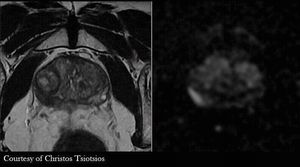

High-resolution, multiparametric (anatomical, functional and quantitative) MR Imaging of the prostate gland. Figure shows a lesion on the peripheral zone with low signal on axial T2-w FSE, high signal on DWI b1400 and low signal on corresponding ADC map (not shown here), findings that indicate malignancy.